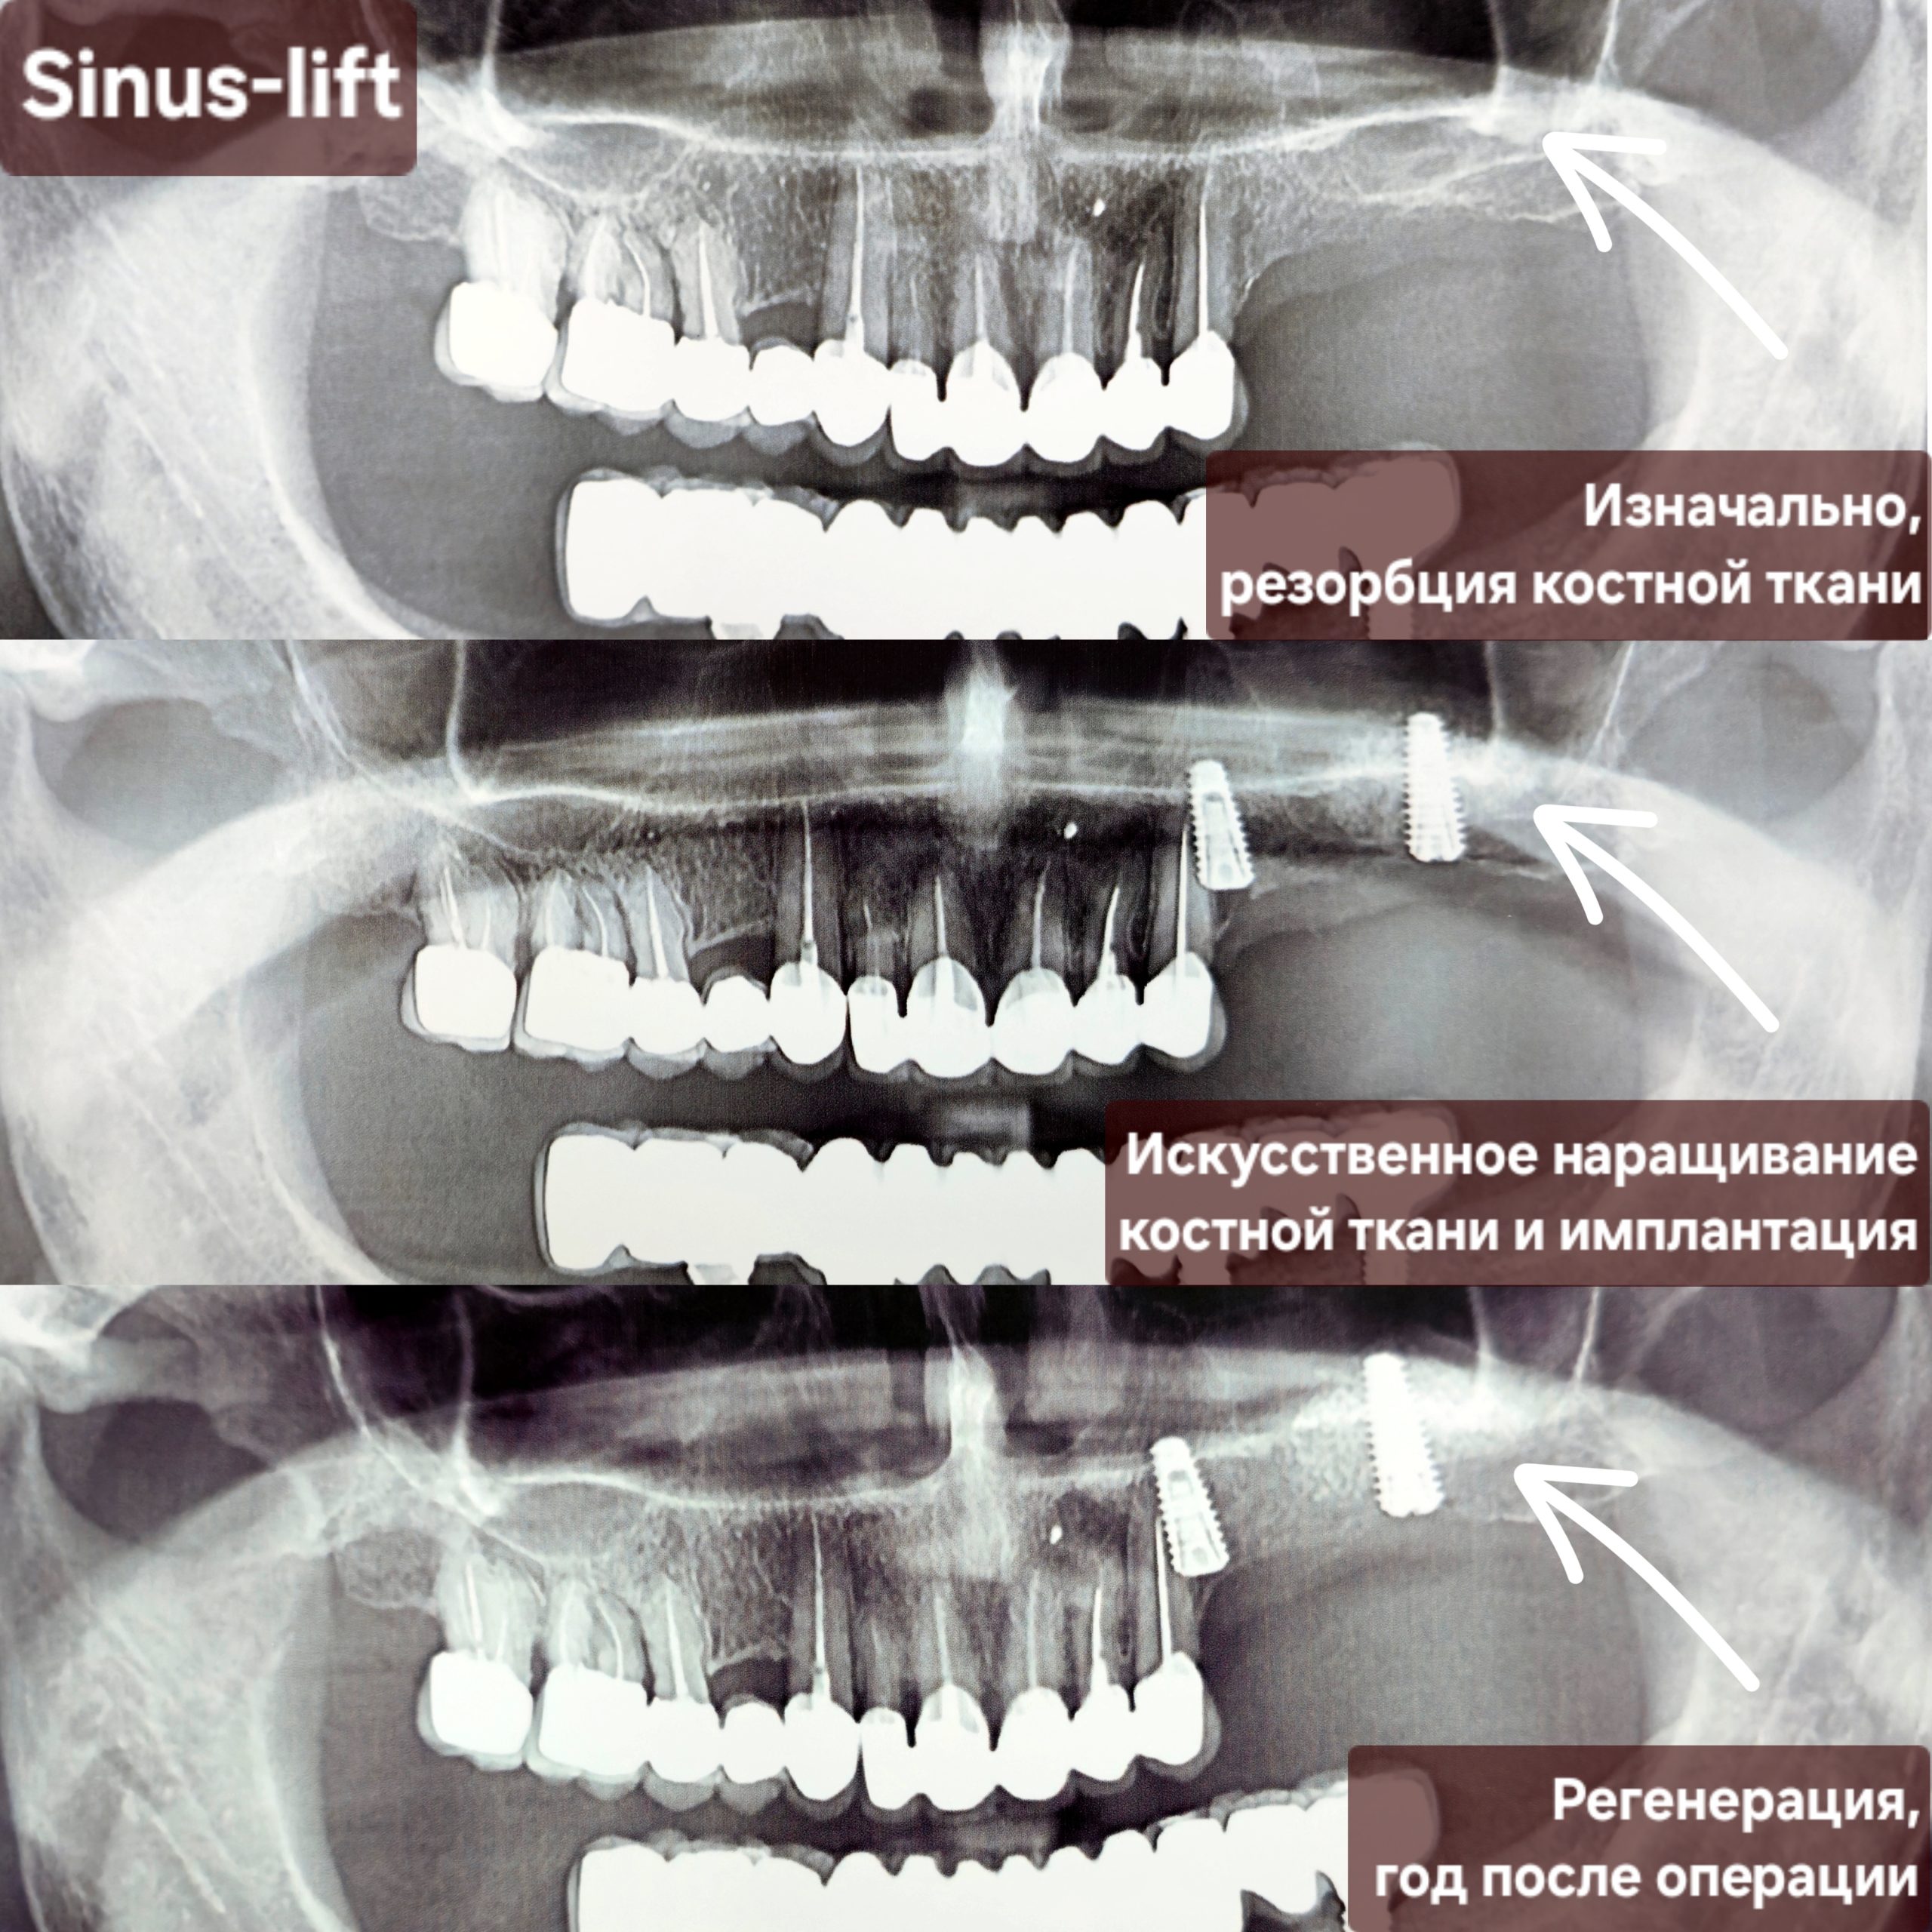

Cea mai răspândită intervenție de augmentare osoasă în stomatologie este operația de sinus lift (ridicarea sinusului) – o procedură chirurgicală de adiție osoasă realizată la maxilarul superior pentru a crește volumul osos necesar inserării implanturilor dentare. Prin ridicarea membranei sinusale și introducerea unui material de grefare, se creează o bază solidă, fiind necesară când sinusurile sunt prea coborâte sau osul este prea subțire. Scopul acestei proceduri este crearea unui suport stabil pentru implanturi dentare în zona laterală superioară (molari/premolari). Procedura de adiție osoasă se efectuează sub anestezie locală. Vindecarea durează de obicei între 4 și 6 luni.

Implantarea și ridicarea sinusurilor permit restabilirea zâmbetului estetic chiar și în cazurile extrem de dificile, adică și în situațiile când pacientul se adresează tardiv. Înainte de apariția acestei tehnici, unii pacienți trebuiau să se mulțumească doar cu proteze și punți mobilizabile. Odată apărută posibilitatea creșterii osoase, contraindicațiile pentru instalarea implantelor au fost considerabil reduse.